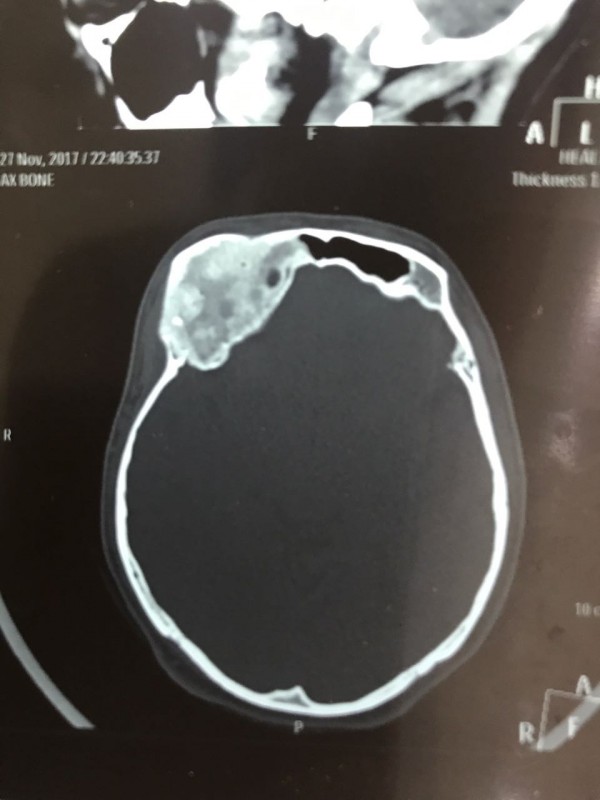

"Компьютерная томография показала, что костная опухоль поражала лобную кость и "крышу" орбиты глаза, которая, в свою очередь, сдавливала глазное яблоко. Чтобы убрать опухоль, потребовалось немало времени. Наша задача была сохранить глазное яблоко, зрительный нерв и сосуды. Если неправильно провести операцию и неправильно закрыть дефект, то в последующем это может привести к эстетической неполноте и асимметрии лица. Уникальность еще и в том, что в операции применялась 3D-стереолитография, которая делается только в Алматы", - рассказал он.

Снимок черепа. Опухоль с левой стороны. Фото предоставлено Константином Ли

Снимок сделан до операции. Фото предоставлено Константином Ли